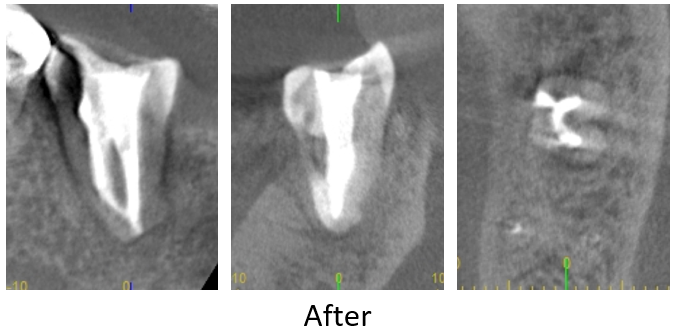

| 患者様データ | 60代 男性 |

| 来院時の主訴 | 「右下の歯が噛むと痛い。」 |

| 医院の診断 | セメント質剥離を併発した歯根破折 |

すでに歯根破折を起こしている歯のため、かなりシビアな状態ではありますが、患者様の強い要望により歯牙再植を応用した方法により歯の保存を行いました。 |